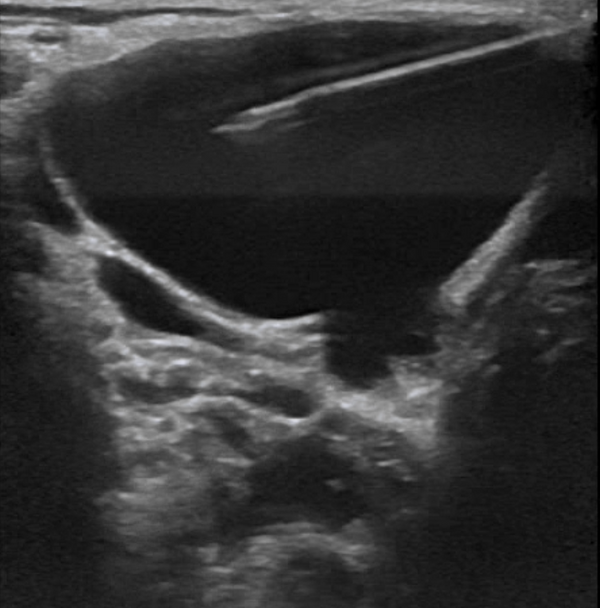

Ультразвуковое исследование: ЛМ классифицируются по данным исследования как макрокистозные, когда отдельные аномальные каналы превышают 10 мм в диаметре, и как микрокистозные, когда отдельные каналы имеют размер менее 10 мм; возможно также сочетание обоих типов. Макрокистозные формы визуализируются как многодольчатые кистозные образования, тогда как микрокистозные очаги выглядят нечёткими и гиперэхогенными из-за множества перегородок между мелкими стенками кист. Микрокистозные формы обычно характеризуются большей инфильтрацией и склонностью к внутренним кровоизлияниям. Смешанные очаги включают как кистозные, так и солидные компоненты, что связано с размером кист и их формой при ультразвуковом исследовании. Цветовое допплеровское картирование позволяет выявлять сосудистые каналы внутри перегородок. В случаях геморрагических или воспалительных осложнений в кистах могут наблюдаться уровни жидкости[6].